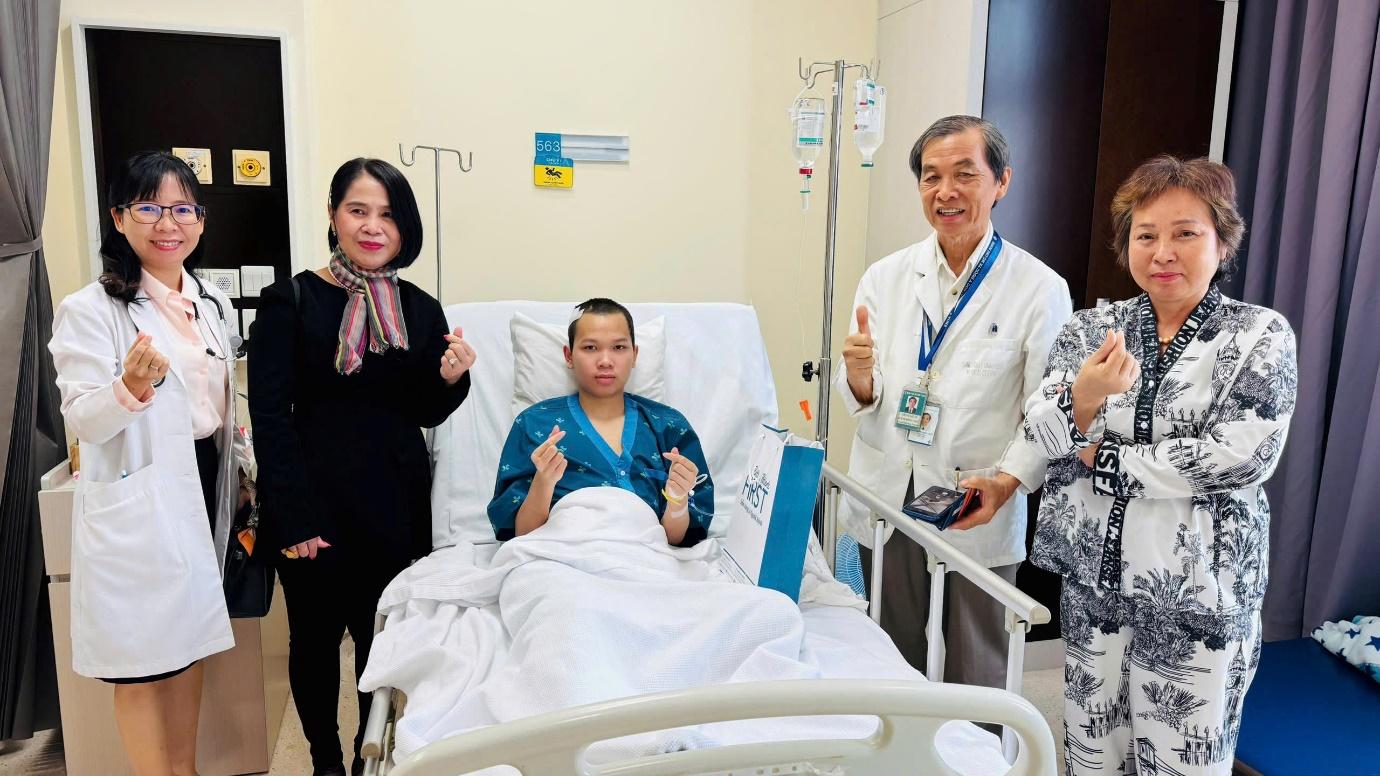

May mắn được phát hiện và điều trị kịp thời tại Việt Nam, bệnh nhân Siek Channa Sak đã hồi phục nhanh chóng chỉ sau vài ngày sau phẫu thuật. Ảnh: BV

Trước đó, bệnh nhân đã trải qua hai cuộc phẫu thuật tại Campuchia do các triệu chứng kéo dài như đau đầu, mờ mắt, yếu tay chân và bí tiểu phải đặt ống thông nhưng không cải thiện. Theo bác sĩ Huỳnh Hồng Châu, hội chứng Arnold-Chiari là một dị tật bẩm sinh hiếm gặp của hệ thần kinh trung ương. Nếu không được phát hiện và điều trị kịp thời, bệnh nhân có thể gặp các biến chứng nặng nề như liệt, rối loạn cảm giác, tàn phế, thậm chí tử vong. May mắn, bệnh nhân được phát hiện và điều trị kịp thời tại Việt Nam nên đã hồi phục nhanh chóng.

Chỉ vài ngày sau phẫu thuật, bệnh nhân tỉnh táo, có thể đi lại và tự đi tiểu. Sau một tuần xuất viện, bệnh nhân tái khám trong tình trạng khỏe mạnh, đi lại bình thường, thị lực cải thiện và không cần hỗ trợ trong sinh hoạt hàng ngày.